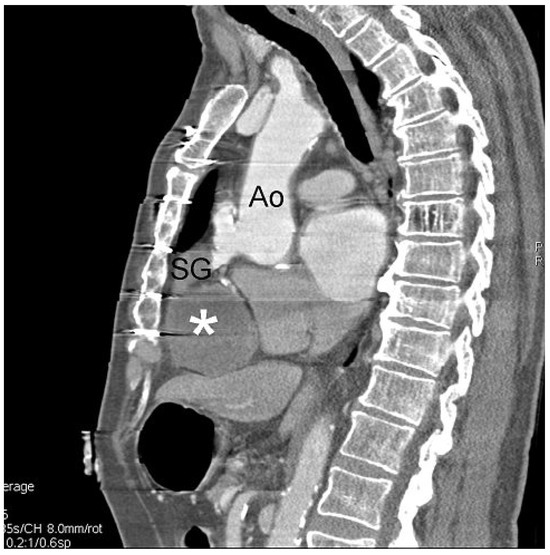

Understanding the pathways that chauffeur pathological remodelling in the failing heart still remains challenging. Myocardial inflammation is a common cause of pathological tissue remodelling in the heart promoting development of heart failures, ofte...